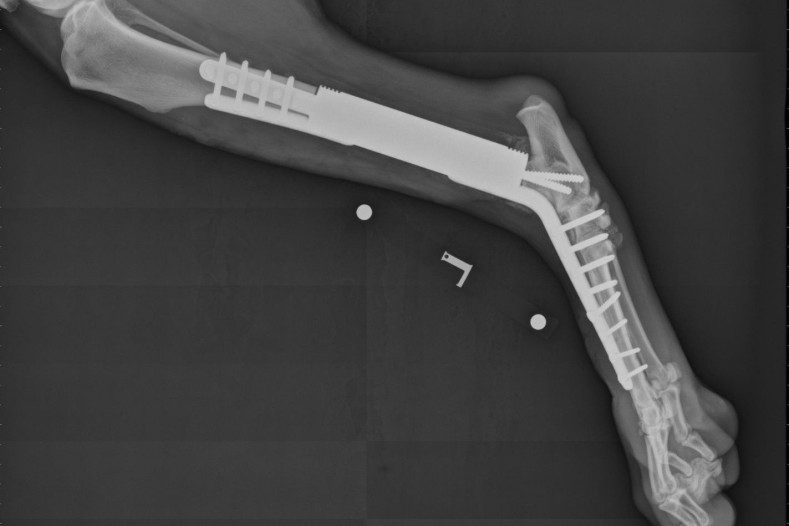

X Ray Dog Pain Relief Dog Osteosarcoma Learn about osteosarcoma, a malignant bone tumor that affects large breed dogs, and its signs, diagnosis, treatment, and prognosis. Amputation is the single best pain relief measure for dogs with appendicular osteosarcoma. One option is radiation therapy. Treatment of canine osteosarcoma has two goals—relief from pain and curative intent. The optimal protocol for palliative radiation in dogs is not known.. Pain Relief Dog Osteosarcoma.